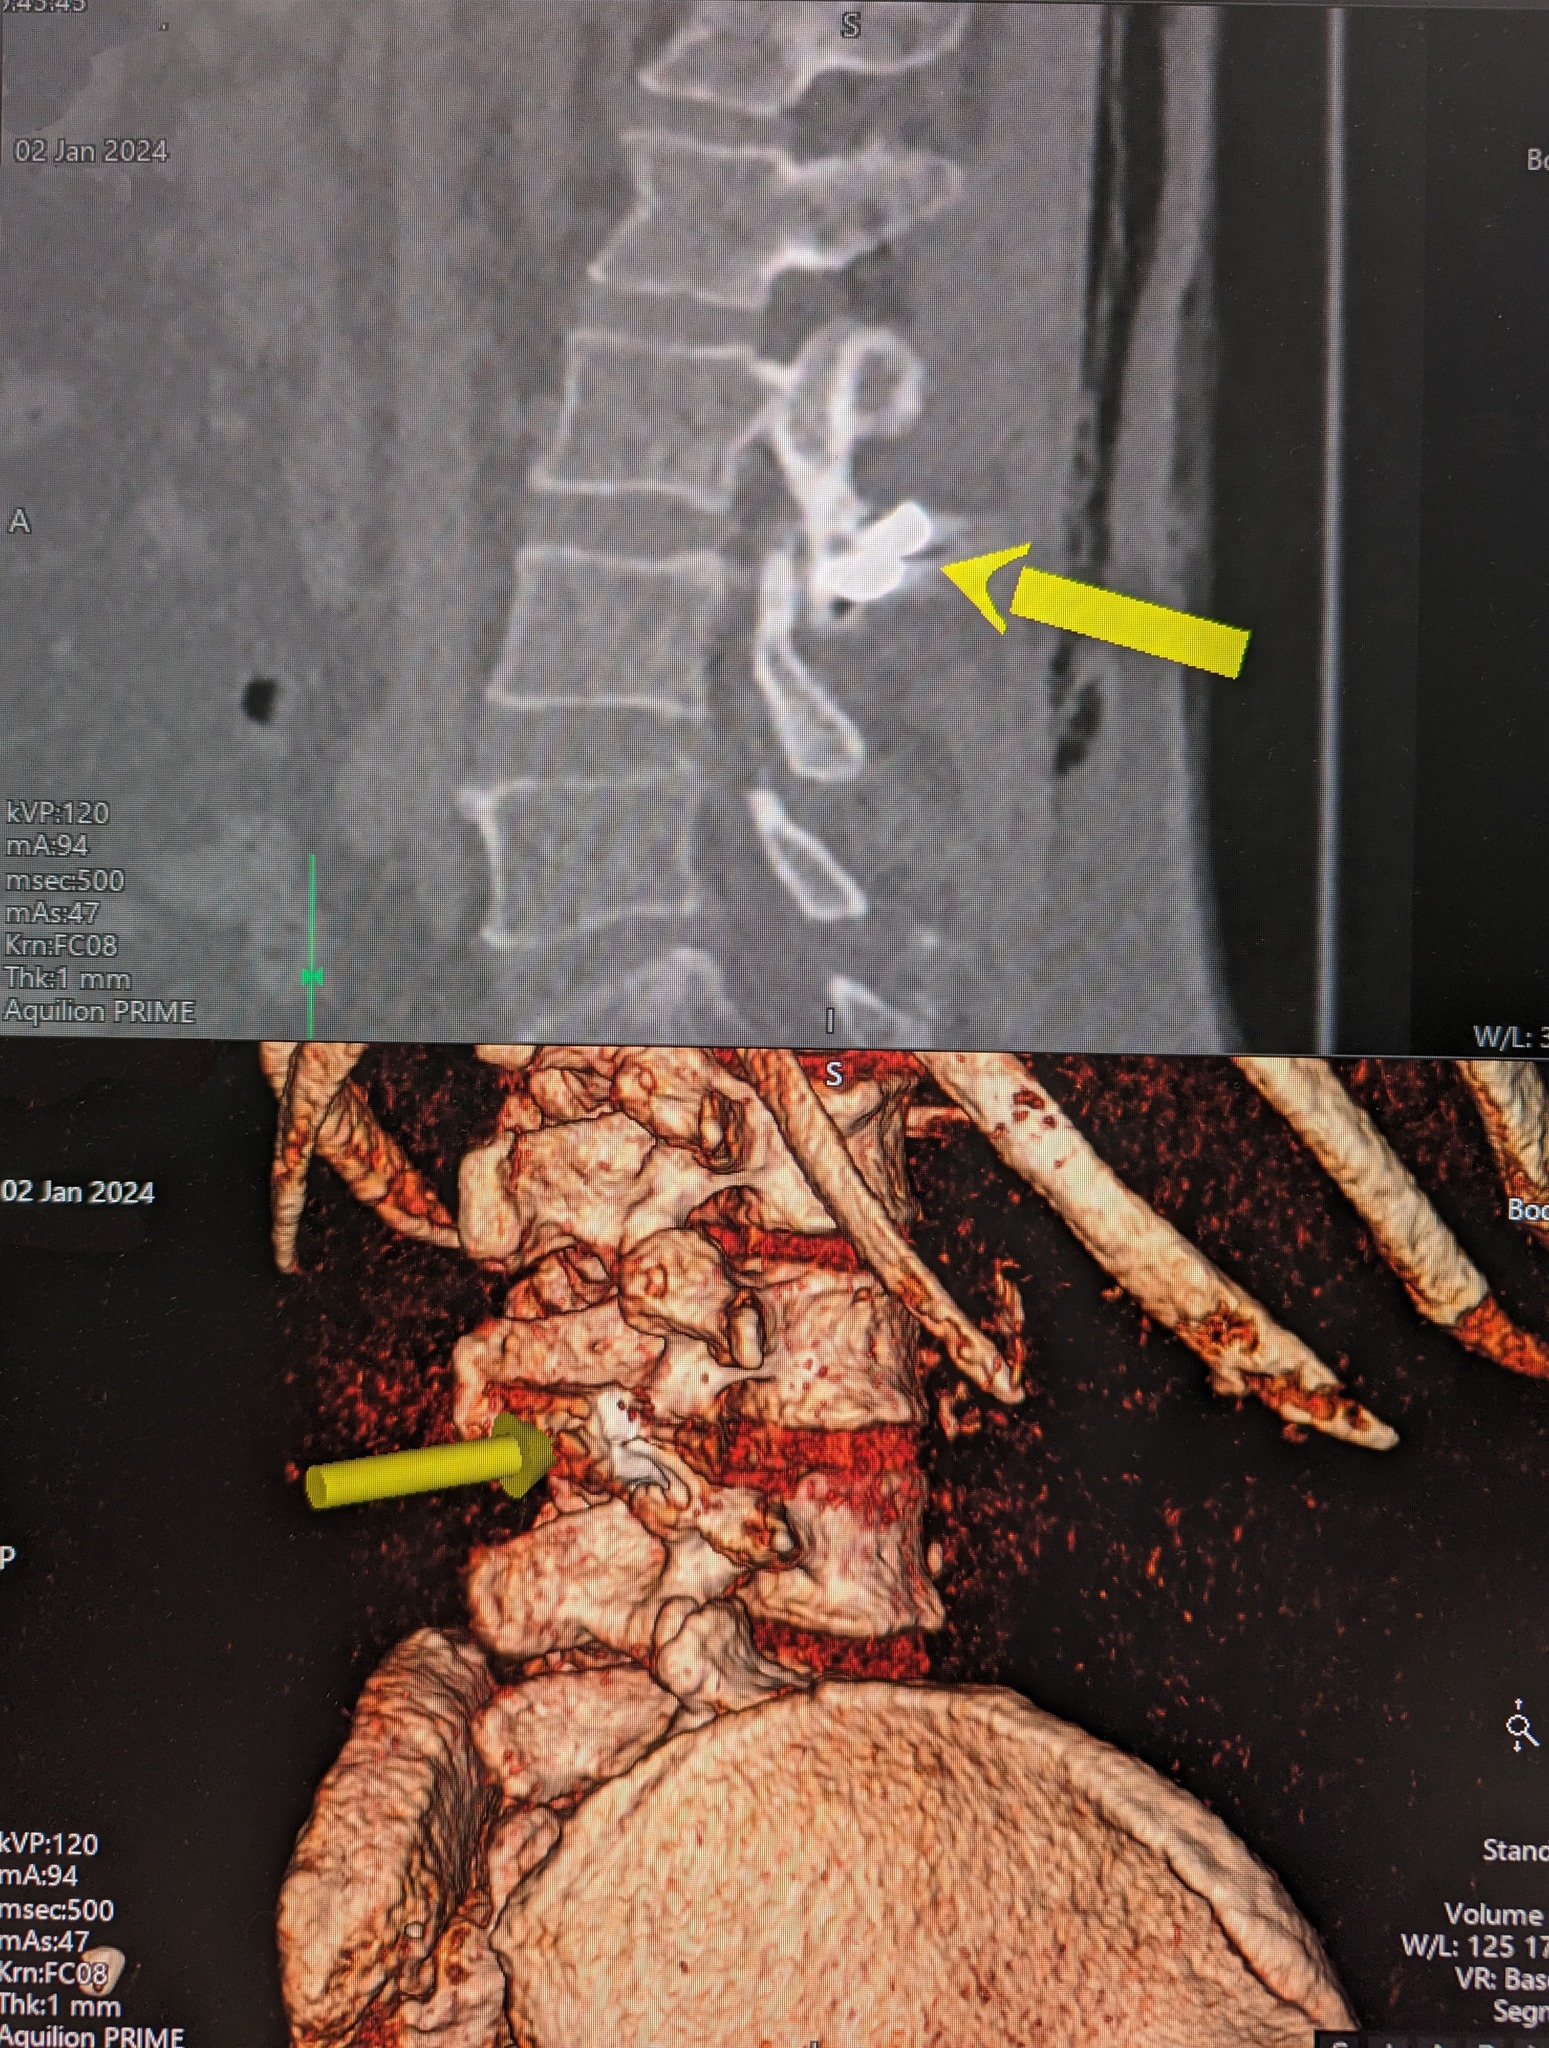

Один из раненных вчера мужчин остался с обломком ракеты в спине - металл застрял в фасеточном суставе между позвонками L3 и L4.

Благодаря компьютерной томографии (КТ) и электронно-оптическому преобразователю обломок был четко локализован. Это дало возможность провести точечную операцию по удалению куска металла.